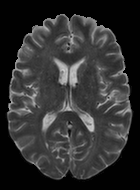

We observed that memberships predicted with an FC layer result in more false positives compared to a fully convolutional network. An example is shown in Fig. 2, where lesion memberships are generated from MPRAGE and FLAIR using the proposed model of convolutional pathways and a comparable model where the last convolutional pathway after concatenation (see Fig. 1) is replaced with a FC layer predicting voxel-wise memberships. The membership image generated with an FC layer, although being close to inside the lesions, has high values () in the left and right frontal cortex where the FLAIR image shows some artifacts. However, the membership obtained with the proposed method shows relatively low values near the frontal cortex.

With FC layer, voxel-wise predictions are performed for each voxel on a new image. Therefore the prediction time for the whole image comprising millions of voxels can take some time even on a GPU, as mentioned in Wachinger et al. (2017). In contrast, with fully convolutional prediction, lesion membership estimation of a mm3 MR volume of size takes only a couple of seconds. Note that although patches are used for training, the final trained model contains only convolution filters and does not depend in any way on the input patch size. Therefore during testing, the lesion membership of a whole 2D slice, irrespective of the slice size, is predicted at a time by applying convolutions on the whole slice. Without an FC layer, the images need not be decomposed into sub-regions, e.g., Kamnitsas et al. (2017). Consequently, there is no need to employ membership smoothing between sub-regions. In addition, since the training memberships, generated by Gaussian blurring of hard segmentations, are smooth, the resultant predicted memberships are also smooth (Fig. 2 last column).